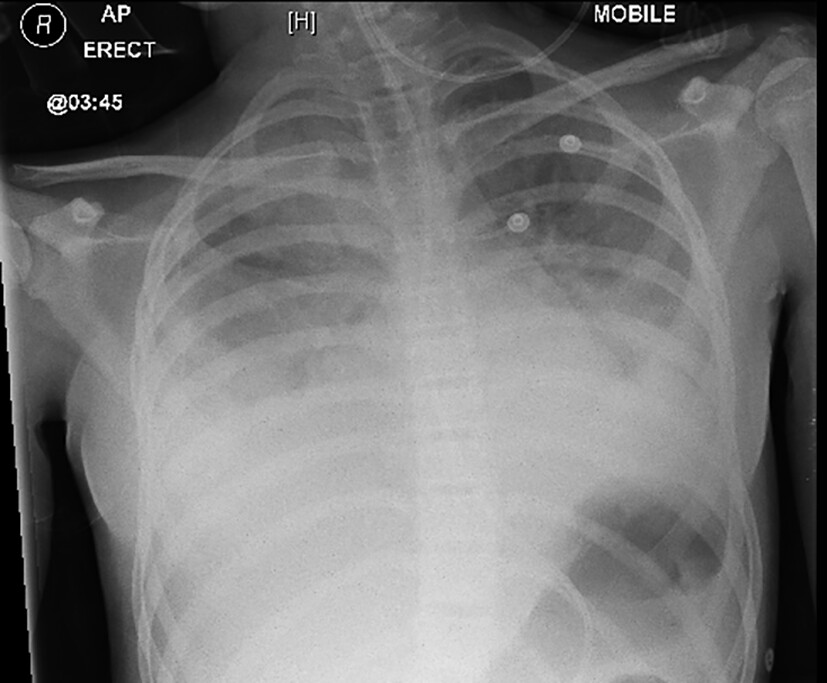

Am Folgetag kommt es zur kardiorespiratorischen Dekompensation (Tachypnoe, Tachykardie, Sättigungsabfall) des Kindes mit zunehmender Enzephalopathie, sodass die Verlegung auf die Intensivstation erfolgt. Bei ausgeprägtem Lungenödem und Pleuraergüssen (Abb. 3) wird mit der Hämofiltration begonnen. In der Echokardiographie ist eine deutlich eingeschränkte systolische Funktion beider Ventrikel erkennbar, das Troponin T ist mit 3329 ng/l (0 – 13 ng/l) stark erhöht. Es folgt eine einwöchige Katecholamin-Pflichtigkeit.